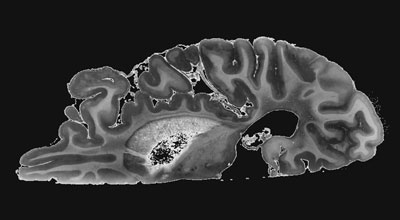

Fellows interested in pursuing career in basic and translational science can conduct research at the Lerner Research Institute Department of Neurosciences led by Dr. Bruce Trapp. Research is mainly focused on the Mellen Center Brain Donation program which contains brains and spinal cords of 200 cases of MS. Research projects can be conducted in MRI-pathology correlation studies, myelination, CNS immune regulation, glial biology, blood brain barrier dysfunction, viral CNS infections, CNS meninges, among other topics.